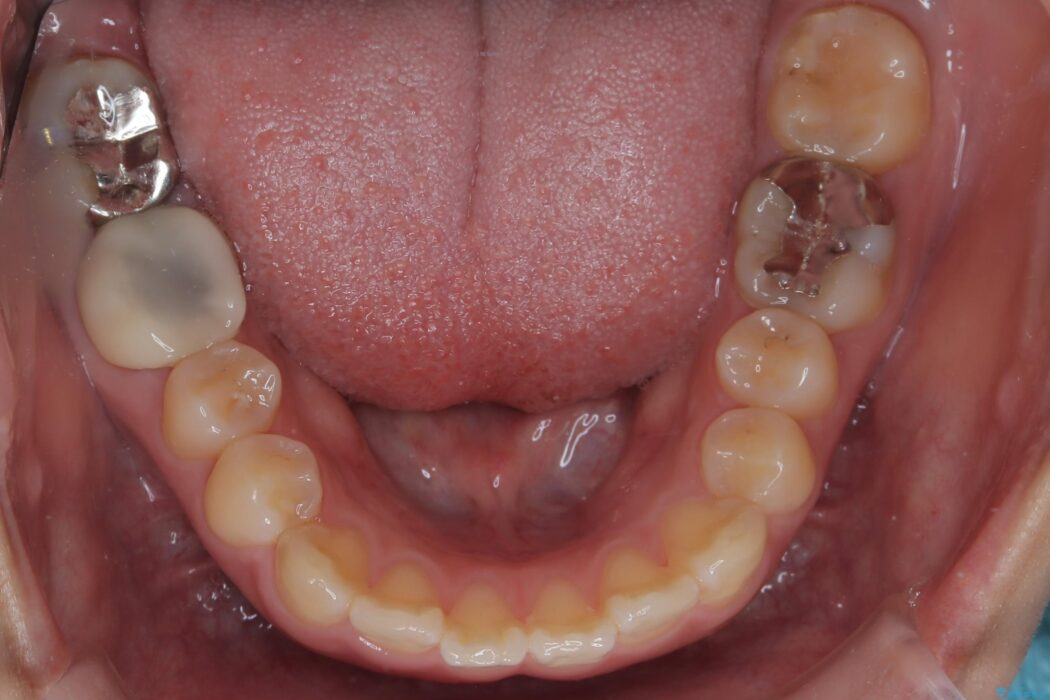

精密検査の結果、前歯を大きく後退させるスペースが必要と診断しました。

「前歯を下げたい」という患者様の強いご希望に応えるため、上下左右の第一小臼歯を抜歯。そのスペースを利用し前歯を奥へ移動させる治療計画を立案しました。

今回の矯正治療では、前歯を大きく後退させるスペースを確保するため、計画通り上下左右の第一小臼歯を抜歯しました。